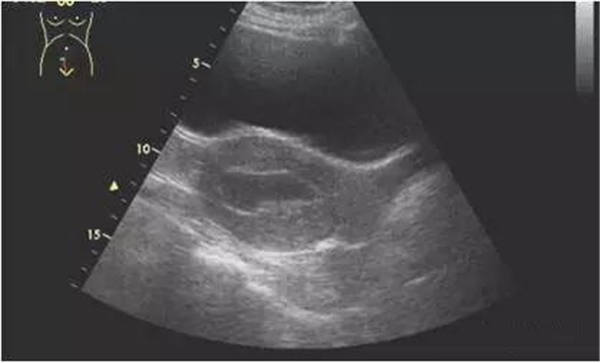

将探头置于剑下偏向右侧,扫描平面与下腔静脉平行,图像显示右房、下腔静脉及肝静脉。正常状态时,下腔静脉伴随深吸气出现明显的塌陷,IVC 直径≤2.1 cm 且吸气塌陷率>50%,即3 mmHg (范围 0-5 mmHg)。当右房压升高时,直径可>2.1 cm和/或吸气塌陷率<50% ,即15 mmHg (范围 10-20 mmHg)。在IVC 直径和塌陷率不适合此标准的情况下,可取中间值 8 mmHg(范围 5-10 mmHg)。

IVC吸气塌陷率的计算:(Max D-Min D)/Max D * 100%